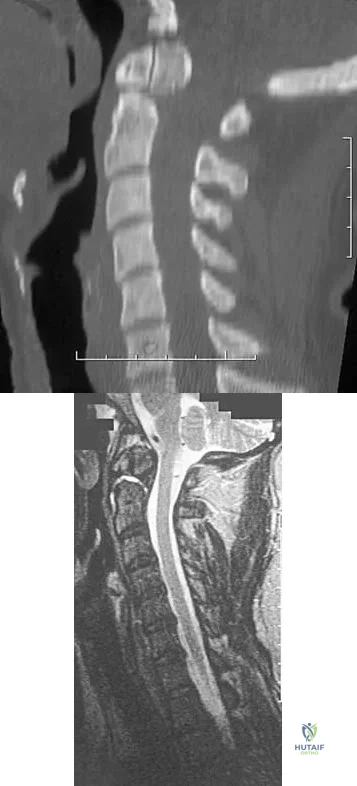

A 42-year-old woman reports that she has low back pain and had a transient loss of consciousness after falling off a horse. She denies having neck pain but notes that she was involved in a motor vehicle accident 2 years ago and had neck pain at that time. Examination reveals full range of motion of the neck and no localized tenderness. The neurologic examination is normal. A lateral radiograph of the cervical spine is obtained. Figures 41a and 41b show CT and MRI scans. What is the most likely diagnosis?

Explanation